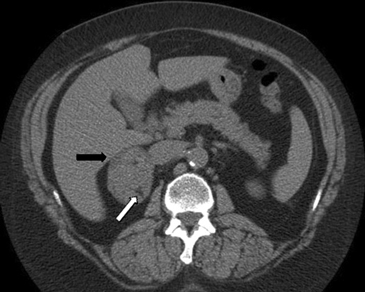

En la TC no contrastada las glándulas suprarrenales normales son homogéneas y simétricas, con una densidad muy similar a la del parénquima renal adyacente (Figura 1 a). Con un medio de contraste ev la glándula suprarrenal se opacifica en forma homogénea, similar al hígado o al bazo (Figura 1 b). Si la cantidad de tejido adiposo retroperitoneal es abundante las glándulas suprarrenales pueden aparecer enteramente rodeadas por grasa y su delimitación es más fácil (Figura 2 a); lo inverso ocurre en pacientes muy delgados con escasa grasa retroperitoneal (Figura 2 b). En RM, en secuencias ponderadas en T1 y T2 convencionales tienen una intensidad de señal homogénea, hipointensa respecto de la grasa adyacente e iso o hipointensa con respecto del parénquima hepático (Figura 3 a y b). En los cortes coronales se aprecia mejor la forma y la posición de las glándulas suprarrenales (Figura 3 c).

Figura 1. Glándula suprarrenal normal en tomografía computada. Cortes axiales de tomografía computada, donde se identifica la morfología normal de la glándula suprarrenal derecha (flecha) en fase no contrastada (a), y tras el uso de medio de contraste endovenoso (b).

Figura 3. Glándula suprarrenal normal en resonancia magnética. (a) Cortes axial ponderado en T1 la señal de la glándula normal (flecha negra) es hipointensa respecto a la grasa retroperitoneal e isointensa respecto al parénquima hepático. (b) Cortes axial ponderado en T2 en que se muestra la glándula suprarrenal derecha (flecha blanca) y (c) corte coronal ponderado en T2 en que se muestra la glándula suprarrenal derecha (flecha blanca) y la glándula suprarrenal izquierda (flecha negra) con similares características de intendidad de señal. 3. Causas y prevalencia de las lesiones suprarrenales